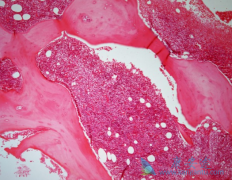

套细胞淋巴瘤 是一种罕见且生长迅速的非霍奇金淋巴瘤,根据美国国家癌症研究所的统计,套细胞淋巴瘤占美国所有非霍奇金淋巴瘤病例的3%-10%。套细胞淋巴瘤是淋巴系统的癌症,套细胞淋巴瘤被诊断出来时,往往已经转移到淋巴结、骨髓和其他器官。 套细 ...